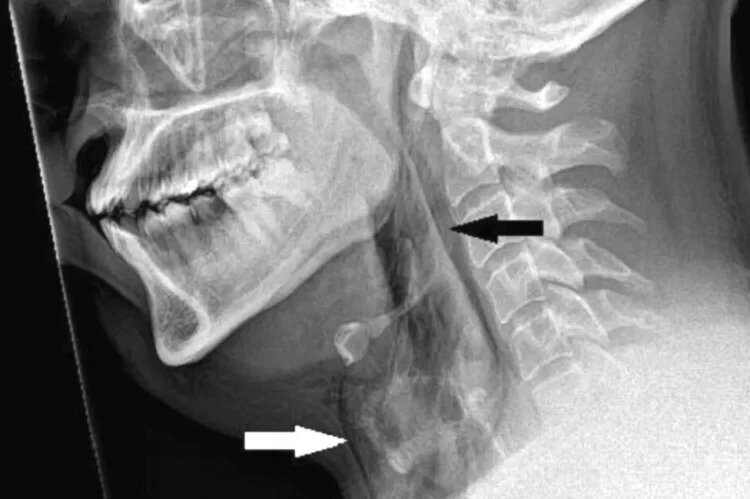

В ходе первого в своем роде медицинского случая мужчина в возрасте 30 лет получил дыру в горле после того, как зажал нос и сомкнул губы, чтобы подавить чихание. Неназванный мужчина был доставлен в больницу Найнуэллс в Данди, Шотландия, с сильной болью после того, как пытался подавить чихание, зажав нос и закрыв рот когда ехал за рулем. Судя по всему, когда вы делаете что-то подобное, давление в верхних дыхательных путях может увеличиться примерно в 20 раз, что может привести к серьезным травмам, включая разрывы барабанных перепонок, аневризмы и даже переломы ребер. Однако в данном конкретном случае у неназванного пациента образовался разрыв трахеи диаметром 2 мм, что вызвало мучительную боль. Разрыв горла, известный в медицине как «спонтанная перфорация трахеи», представляет собой редкую и потенциально опасную для жизни травму, которая раньше не была связана с удушающим чиханием. Когда мужчина прибыл в отделение неотложной помощи, он испытывал сильную боль, шея опухла с обеих сторон и

Когда мужчина прибыл в отделение неотложной помощи, он испытывал сильную боль, шея опухла с обеих сторон и он едва мог пошевелить головой. Он рассказал врачам, что за рулем у него случился приступ сенной лихорадки, и когда у него появилось побуждение чихнуть, он просто сдержал его, ущипнув нос и закрыл рот. В итоге у него было порвано дыхательное горло.

Осматривая пациента, врачи услышали слабый потрескивающий звук горла, указывающий на то, что что-то не так. К счастью, это состояние не мешало дышать, глотать или говорить. После диагностики пациента выписали, назначили обезболивающие и лекарства от сенной лихорадки с рекомендацией воздерживаться от физической активности в течение двух недель. Пять недель спустя он вернулся на осмотр, после чего мужчине сказали что все впорядке.